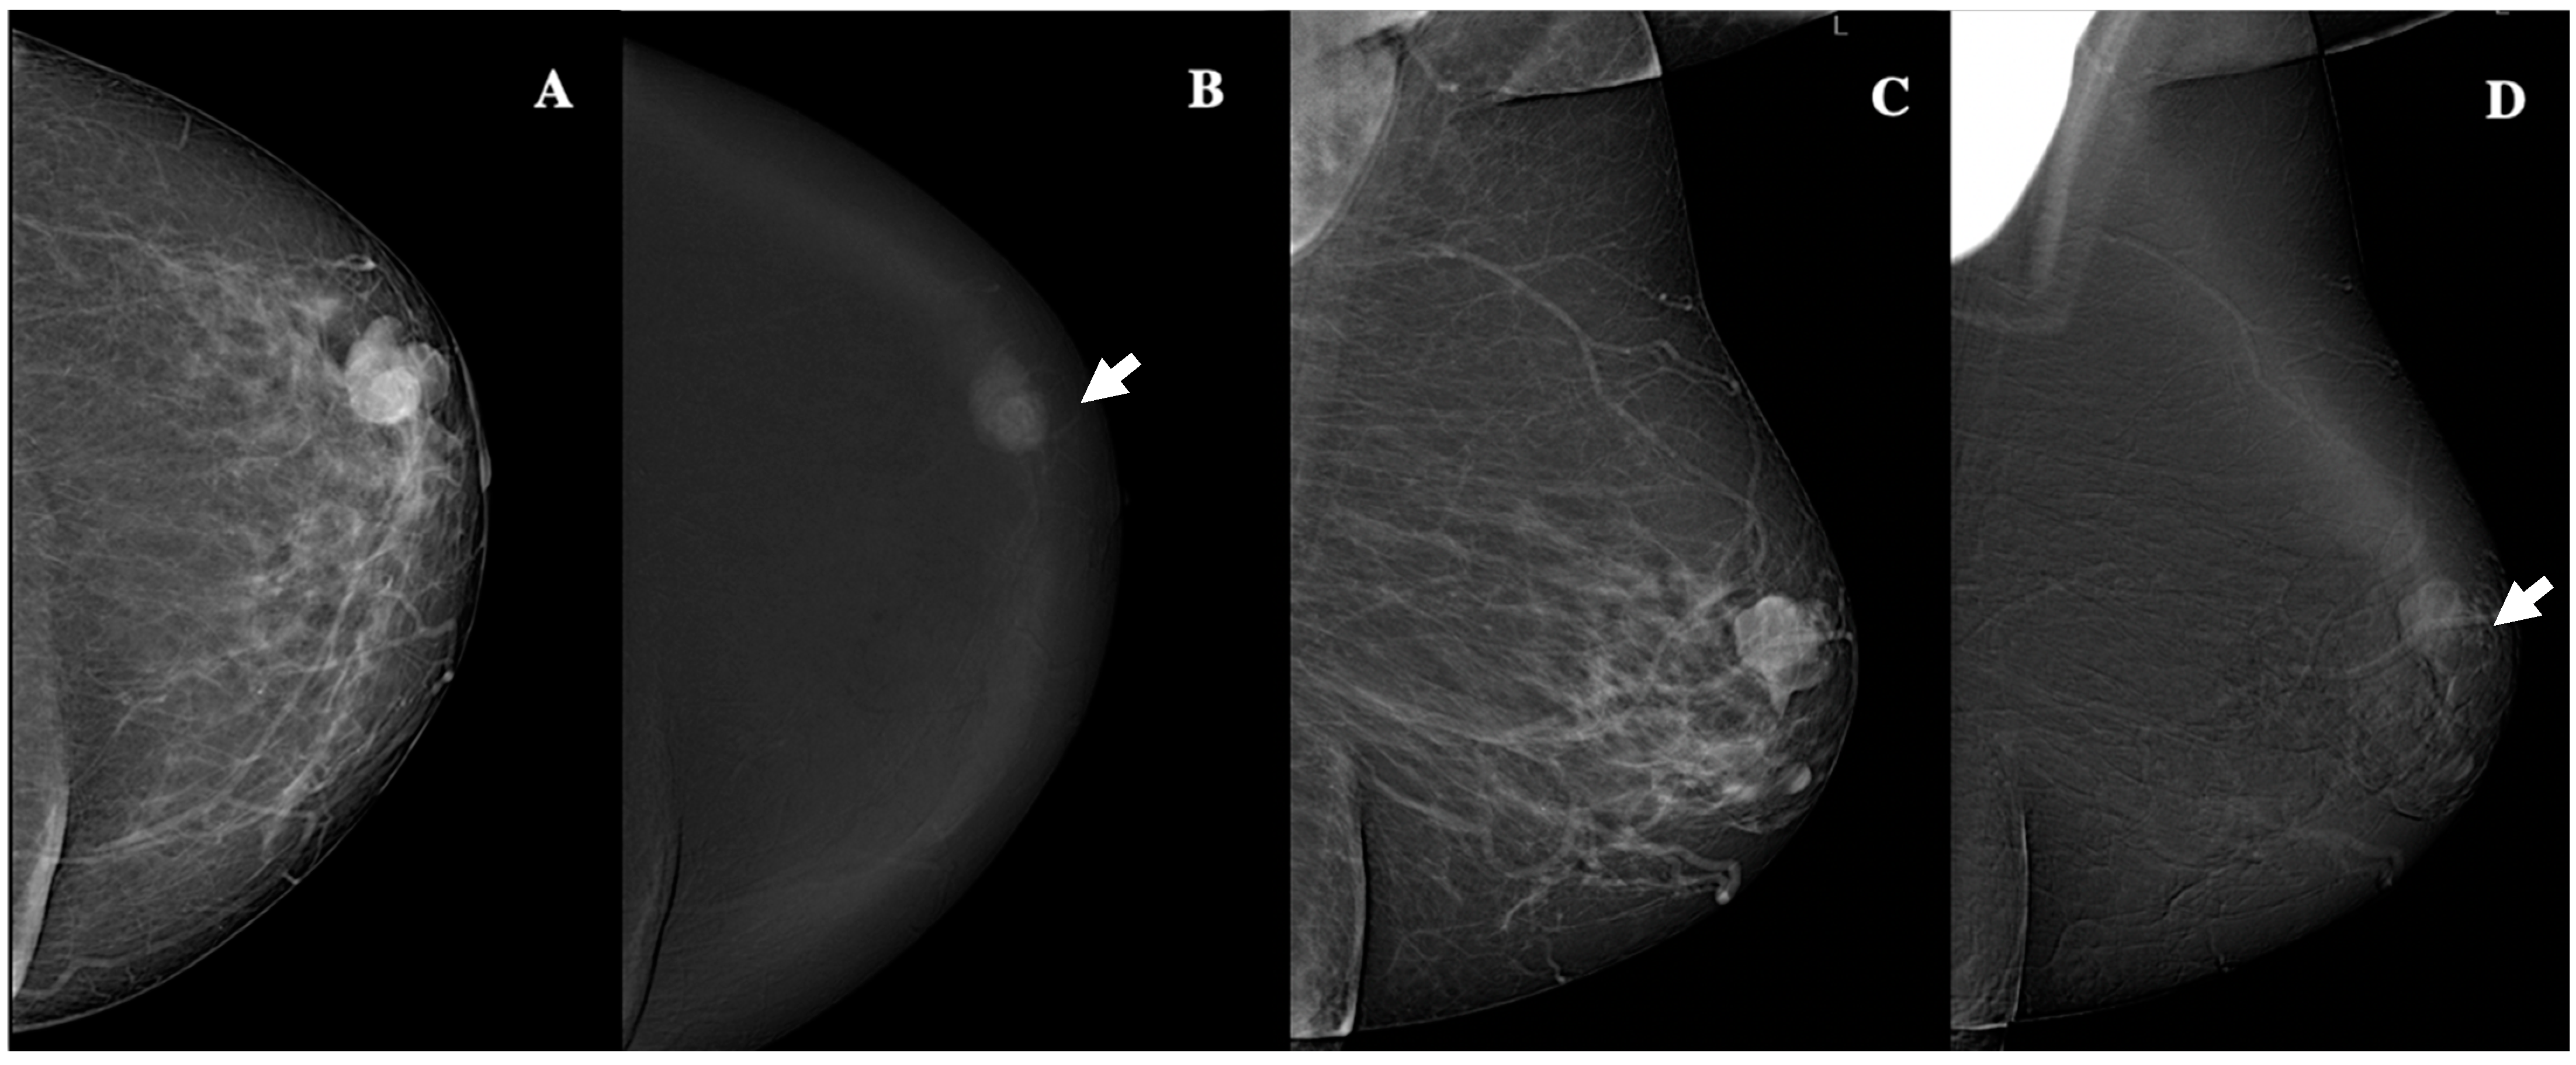

| Lesion shape | Oval (n, %)/round (n, %)/irregular (n,%) | 31 (62%)/9 (18%)/10 (20%) |

| Lesion margins | NC (n, %)/C (n, %) | 7 (14%)/43 (86%) |

| Lesion internal enhancement | Homogeneous (n, %) | 8 (16%) |

| Heterogeneous (n, %) | 37 (74%) | |

| Rim enhancement (n, %) | 5 (10%) | |

| Lesion enhancement conspicuity | Low (n, %) | 25 (50%) |

| Moderate (n, %) | 10 (20%) | |

| High (n, %) | 15 (30%) | |